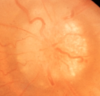

O que é papiledema?

É o edema de papila associado à hipertensão intracraniana

Quais as características do papiledema inicial?

Edema + hiperemia (I-S-N-T)

Desaparecimento do pulso venoso espontâneo

Quais as características do papiledema bem desenvolvido?

↑Edema

Hemorragias e exsudatos

Engurgitamento vascular/obscurecimento dos vasos

Quais as características do papiledema crônico?

↓Edema

↓Hemorragias/Exsudatos algodonosos

Surgem Exsudatos duros (pseudodrusas)

Quais as características do papiledema atrófico?

↓ Edema e espessura CFNR

Palidez

Estreitamento vascular

Quais características diferenciam o papiledema verdadeiro do pseudopapiledema?

Hiperemia

Alterações microvasculares/Hemorragias/Exsudatos

Obscurecimento dos vasos